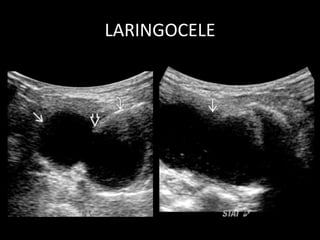

LARINGOCELE

LARINGOCELE • Evaginación dela mucosa normal laringea que se proyecta superiormente desde ventrículo laríngeo. • Contiene numerosas glándulas mucosas • laringocele interno: – Aire dilatada o laríngea sáculo lleno de líquido – Situado en el espacio paraglótico de supraglotis